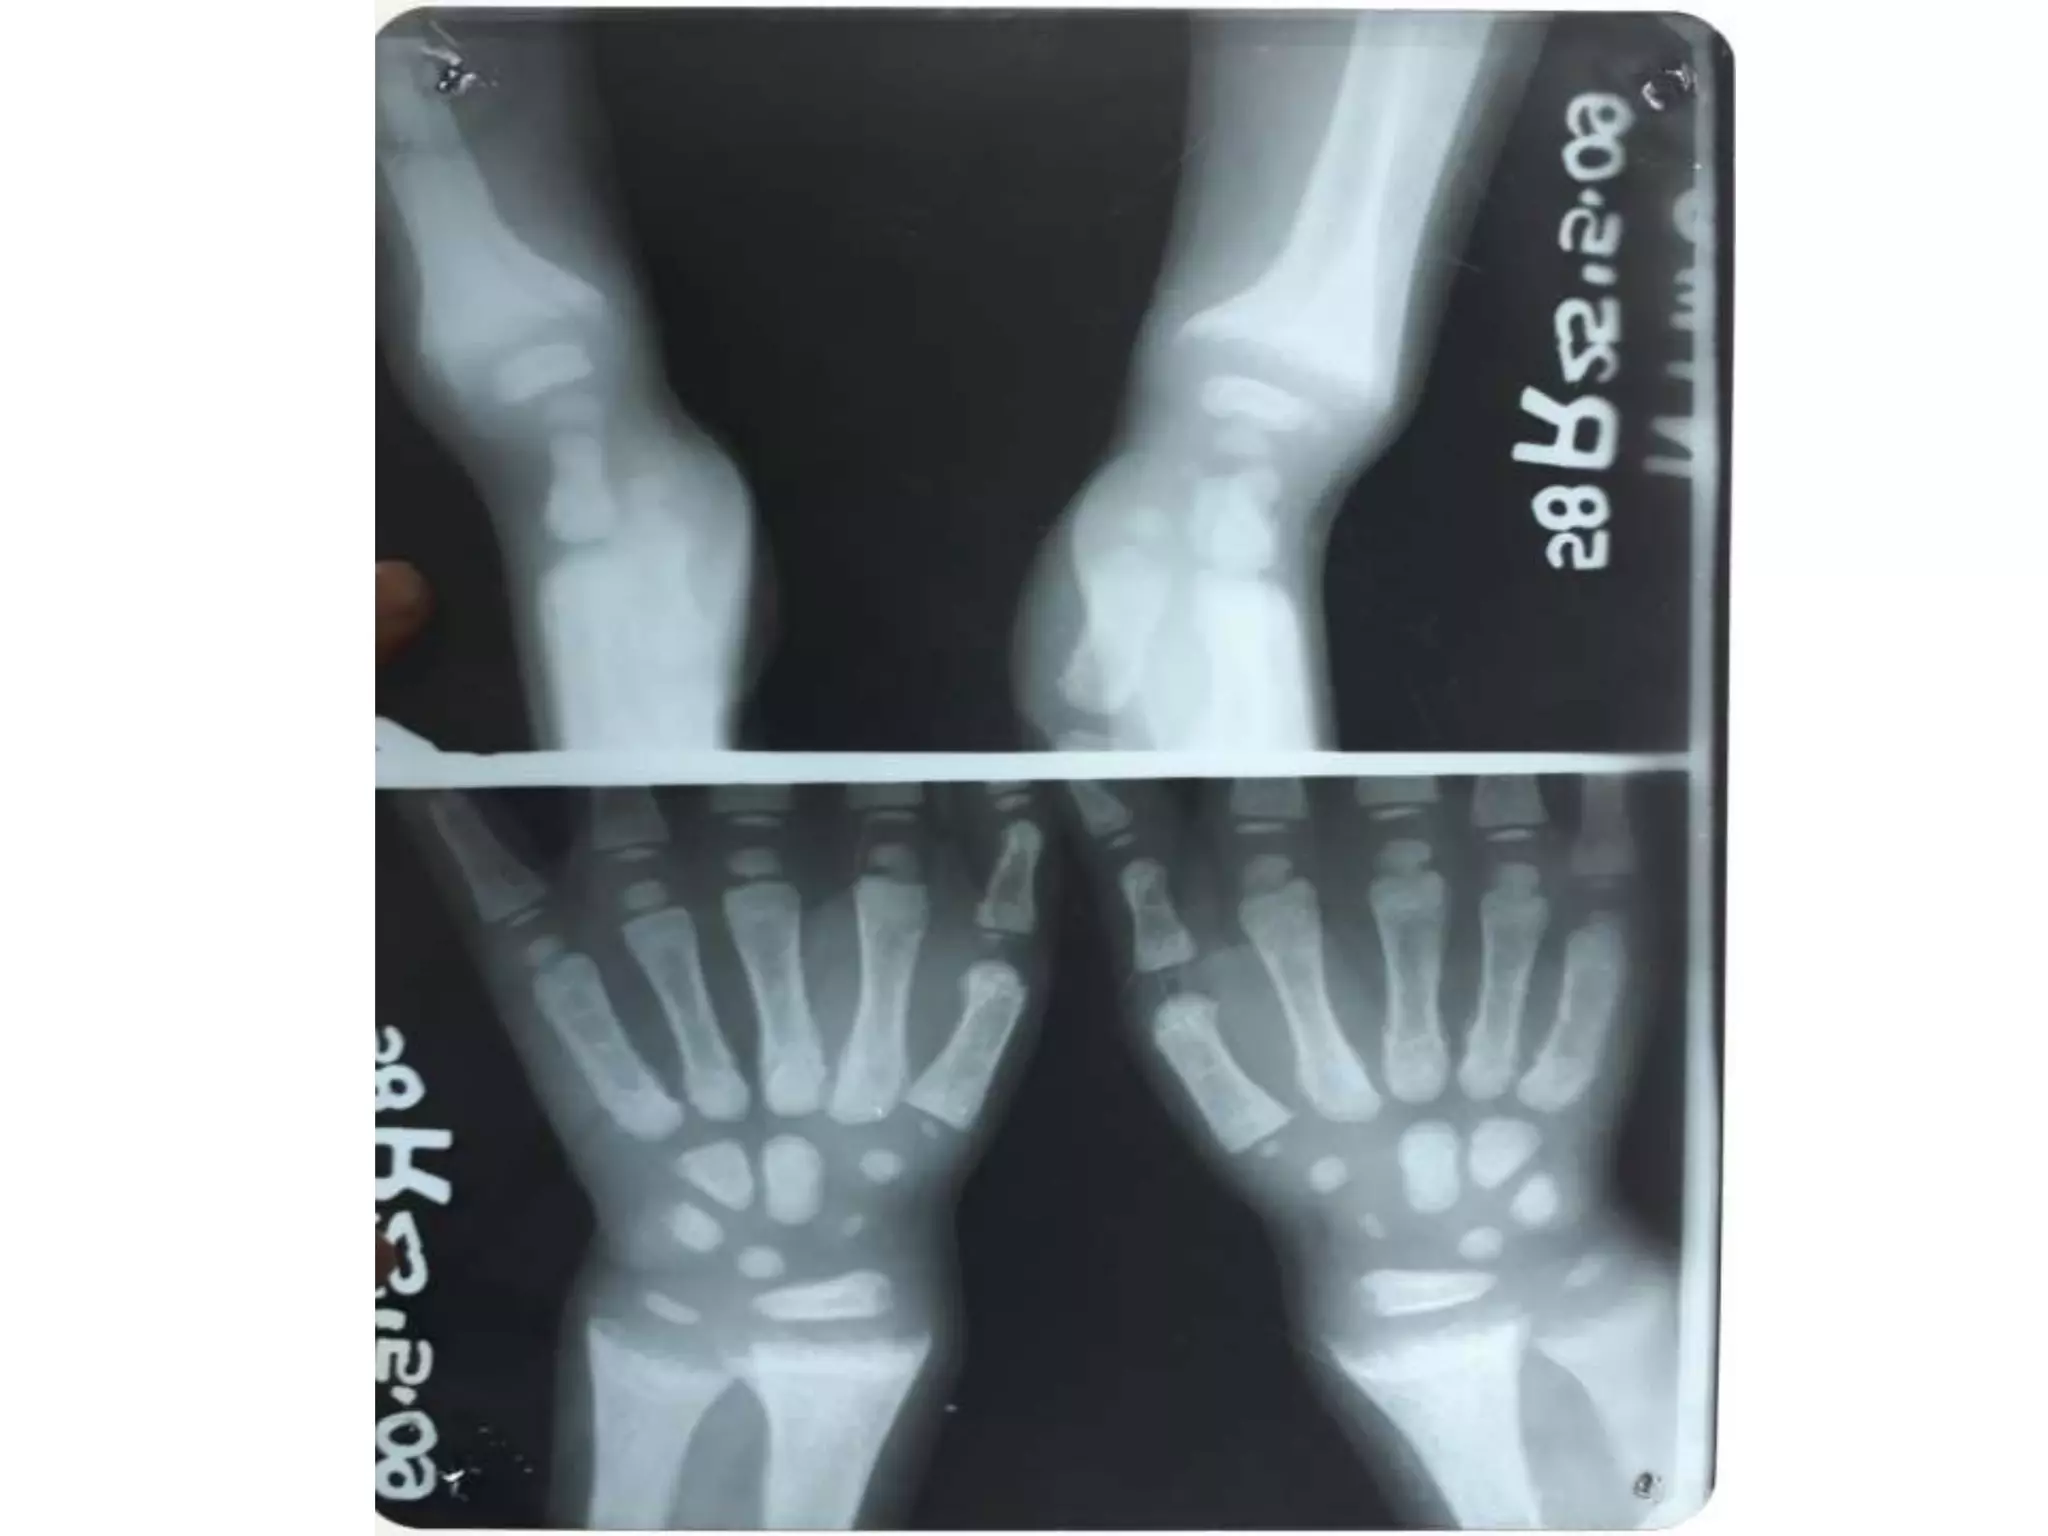

SCURVY

• Generalised osteopenia

• cortical thinning: “pencil-point” cortex

• Periosteal reaction due to subperiosteal

haemorrhage

• scorbutic rosary: expansion of the

costochondral junctionsmay relate to the

fracturing of the zone of provisional

calcification during normal respiration

• similar to the rachitic rosary appearance as

seen in rickets

• Haemarthrosis

• Wimberger ring sign: circular, opaque

radiologic shadow surrounding epiphyseal

centres of ossification, which may result

from bleeding

• Frankel line: dense zone of provisional

calcification

• Trümmerfeld zone: lucent metaphyseal band

underlying Frankel line

• Pelken spur: metaphyseal spurs which result

in cupping of the metaphysis

SCURVY • Generalised osteopenia •cortical thinning: “pencil-point” cortex • Periosteal reaction due to subperiosteal haemorrhage • scorbutic rosary: expansion of the costochondral junctionsmay relate to the fracturing of the zone of provisional calcification during normal respiration • similar to the rachitic rosary appearance as seen in rickets • Haemarthrosis • Wimberger ring sign: circular, opaque radiologic shadow surrounding epiphyseal centres of ossification, which may result from bleeding • Frankel line: dense zone of provisional calcification • Trümmerfeld zone: lucent metaphyseal band underlying Frankel line • Pelken spur: metaphyseal spurs which result in cupping of the metaphysis